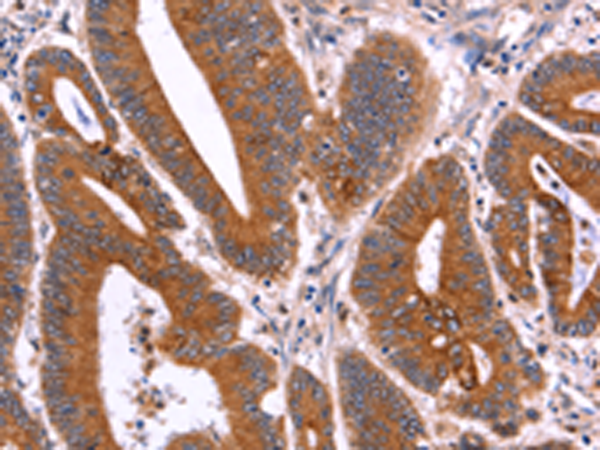

分类: 科研抗体货号: P08183别名: COT应用: WB,IHC反应种属: Human, Mouse, Rat